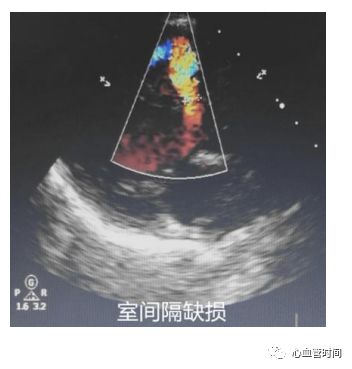

室间隔观察有无异常血流,室缺时可在该切面见到

花彩血流束穿过室间隔射向右室。

室间隔观察有无异常血流,室缺时可在该切面见到

花彩血流束穿过室间隔射向右室。